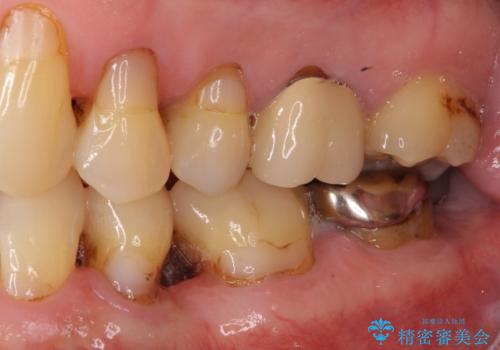

検査を行ったところ、前歯1本は周辺の骨が失われており、抜歯が必要でした。

上顎の奥歯は全体的に歯周ポケットが散見され出血が認められたため、歯周外科処置を行うこととしました。

上の歯は見た目を良くしたいというご希望があったため、歯周外科処置を行った歯についてはセラミッククラウンで補綴することとしました。